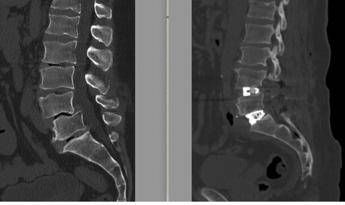

(Adnkronos) – Al Tiberia Hospital di Roma, struttura di Gvm Care & Research accreditata con il Servizio sanitario nazionale, "è stato eseguito con successo un intervento di chirurgia vertebrale di alta complessità su un paziente di 55 anni affetto da una spondilolistesi L4-L5 e grave discopatia L5-S1, associate a un grave sbilanciamento dell'equilibrio sagittale della colonna vertebrale, utilizzando la tecnica Alif (Anterior Lumbar Interbody Fusion – artrodesi intersomatica con approccio combinato anteriore e posteriore) su entrambi i livelli. Una tecnica ancora poco diffusa in Italia, che richiede competenze elevate, ma che consente un recupero funzionale più veloce", descrive una nota. "La struttura romana – si legge – è polo di riferimento per la chirurgia vertebrale complessa e tra i pochi centri in Italia ad eseguire la tecnica Alif; questo intervento conferma il percorso di sviluppo di Tiberia Hospital come riferimento sul territorio per la chirurgia ad alta complessità". Il paziente, di professione traslocatore, svolgeva un'attività fisicamente usurante per la colonna vertebrale e presentava una corporatura particolarmente imponente, con un'altezza di circa 2 metri e un peso superiore ai 120 chilogrammi. Queste caratteristiche, insieme alla deformità della colonna, hanno rappresentato un elemento determinante nella scelta della strategia chirurgica. "In un paziente con questa corporatura e con un lavoro così usurante per la colonna le sollecitazioni biomeccaniche sul rachide sono rilevanti – spiega Federico Caporlingua, neurochirurgo e chirurgo vertebrale nell'équipe neurochirurgica del Tiberia Hospital, insieme ad Alessandro Caporlingua e Gennaro Lapadula – L'approccio anteriore previsto dalla tecnica Alif, sebbene sia più complesso e con rischi intra-operatori maggiori, era quello che offriva le migliori possibilità in termini di stabilità e solidità del sistema impiantato e di risultato clinico nel medio-lungo periodo". La diagnosi era di spondilolistesi tra la quarta e la quinta vertebra lombare (L4-L5), una patologia degenerativa cronica caratterizzata dallo scivolamento progressivo di una vertebra sull'altra, associata a una discopatia del disco intervertebrale L5-S1. Nel tempo – sottolineano gli esperti – questa deformità determinava una compressione significativa delle radici nervose, provocando una sciatalgia bilaterale invalidante, con dolore irradiato agli arti inferiori che peggiorava in posizione eretta e durante le attività quotidiane e lavorative, compromettendo in modo rilevante la qualità di vita. "Questo tipo di chirurgia richiede una padronanza della tecnica di approccio anteriore alla colonna vertebrale, che comporta la manipolazione, tra le altre, di strutture vascolari arteriose e venose, critiche per la vita del paziente – evidenzia Alessandro Caporlingua – I rischi derivanti da questo tipo approccio chirurgico non possono essere trascurati, per questo viene proposto a pazienti selezionati solo quando riteniamo che sia l'unica strategia che consenta di ottenere un risultato accettabile in termini di correzione efficace della deformità, a sua volta migliore garanzia di un risultato duraturo nel tempo dal punto di vista del miglioramento della lombalgia". Un passaggio fondamentale nella pianificazione dell'intervento chirurgico – illustra la nota – è stato lo studio dei cosiddetti 'parametri spino-pelvici', effettuato su una radiografia dell'intera colonna vertebrale. Questi supportano il chirurgo vertebrale nella scelta dell'approccio chirurgico più corretto e della tipologia di impianti da utilizzare in base al grado di lordosi da ripristinare. "Oggi la chirurgia vertebrale non si limita a liberare i nervi o a stabilizzare un segmento ritenuto instabile – precisa il neurochirurgo e chirurgo vertebrale – ma punta a ricostruire un assetto posturale il più possibile fisiologico. Il mancato rispetto e, quando possibile, ripristino di questi parametri può portare nel tempo al fallimento del costrutto impiantato nella colonna vertebrale o alla prematura degenerazione dei segmenti della colonna adiacenti a quello trattato". L'intervento è stato eseguito all'inizio di febbraio 2026 ed è durato circa 6 ore, riferiscono i sanitari. A 12 ore dalla chirurgia è stata eseguita una Tac addominale senza mezzo di contrasto per escludere eventuali complicanze legate all'accesso anteriore, mentre una radiografia in posizione eretta ha consentito di verificare immediatamente la qualità della correzione ottenuta. Il decorso post-operatorio è stato regolare. Il paziente si è risvegliato con un miglioramento sostanziale della sintomatologia sciatalgica e con un dolore limitato alle ferite chirurgiche, gestibile con comuni analgesici. In assenza di complicanze neurologiche o generali, è stato dimesso in seconda giornata post-operatoria. Rientrato a casa, il paziente prosegue il monitoraggio clinico con l'équipe di Chirurgia vertebrale di Tiberia Hospital. Nelle prime settimane, la riabilitazione consiste principalmente nella deambulazione e nella ripresa graduale delle attività quotidiane senza caricare la colonna. "Uno dei vantaggi della tecnica Alif – conclude Lapadula, neurochirurgo e chirurgo vertebrale al Tiberia Hospital – è la maggiore stabilità 'primaria' (quella garantita dall'impianto non appena il paziente esce sala operatoria, consolidato nel corso dei primi 3 mesi dall'intervento grazie al processo di artrodesi, ovvero di deposizione di nuovo materiale osseo a fondere l'impianto con la colonna vertebrale), consentita da gabbie intersomatiche con ampia superficie di appoggio, che distribuiscono meglio i carichi e permettono un ritorno al movimento e al carico in tempi più rapidi, un aspetto particolarmente importante nei pazienti con corporatura importante o con elevate richieste funzionali". Il 55enne – riporta la nota – ha raccontato che tutto è iniziato con un dolore che dal polpaccio risaliva verso l'alto. Un dolore che si è trascinato dietro per diverso tempo finché ha deciso che non poteva più continuare così. Grazie a un suggerimento fortunato ha trovato nell'équipe di Tiberia Hospital la soluzione che gli ha fatto prendere la decisione di operarsi. Al controllo clinico, svoltosi a circa 1 mese dall'intervento, il paziente aveva riguadagnato 4 centimetri in altezza. "Sto proseguendo con la fisioterapia – racconta – Adesso la mia postura è più dritta, dopo anni che non lo era più, sto allenando muscoli e nervi che erano ormai dimenticati! Ci vorrà il tempo che ci vorrà, ma sono sicuro che il dolore che provavo prima appartiene solo al passato e riacquisterò la qualità di vita che non avevo più".